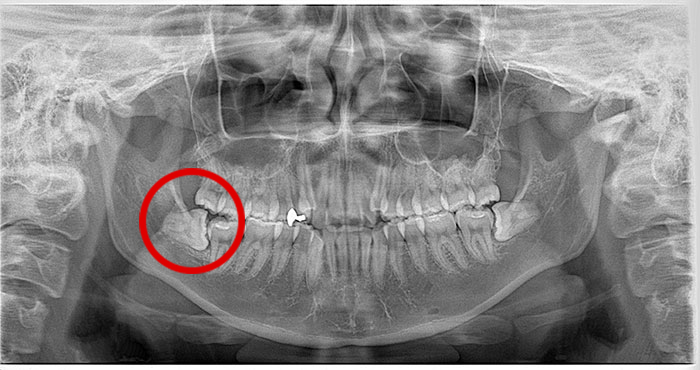

横になった親知らずの症例

Before

After

真横になった親知らずを抜歯したレントゲン写真です。